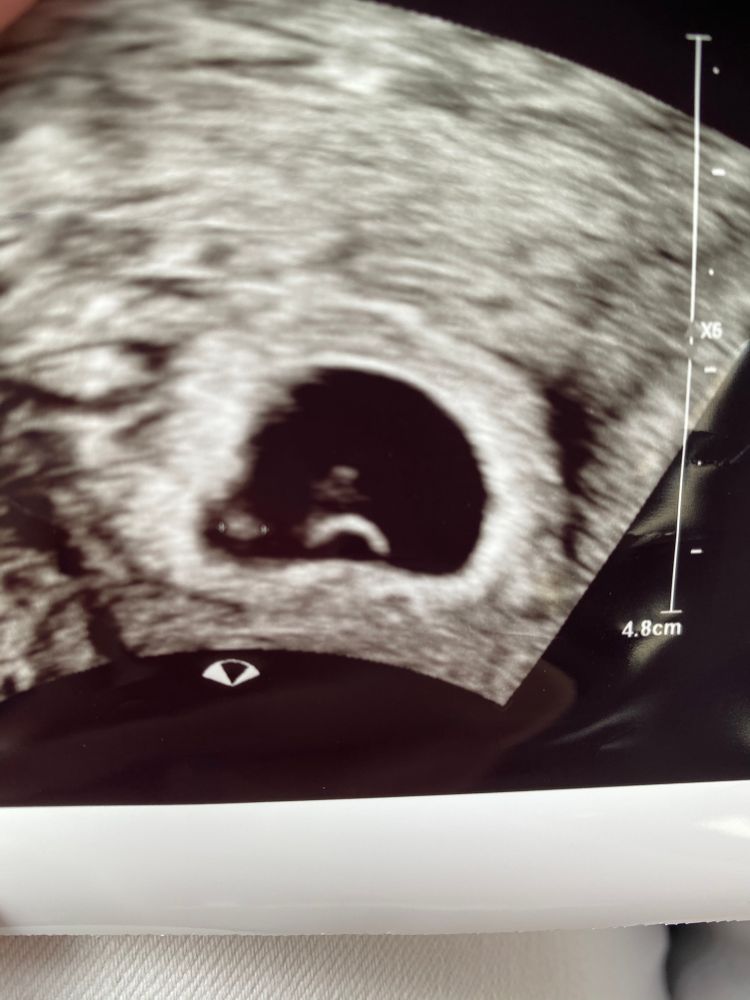

УЗИ, КТГ, доплерДевочки , кто понимает в узи,посмотрите пожалуйста.Слева эмбрион 2 мм, внизу желточный мешочек,а что над ним?? Это случайно не два эмбриона?

Я что то и не спросила у врача, она быстро узи делала. Срок день в день,5 недель 6 дней.

У вас один эмбрион, просто что-то смазано.

Мила, я не ждала сердцебиения 😅у меня вопрос в другом, что на узи, желточный мешочек я вижу, эмбрион и ещё одно включение. А о том что не смотрели эмбрион, я и написала что не вникали о нем, так как рано

Мила, я сама спросила есть ли эмбрион, она то что слева измерила.. а эмбрион вообще же рядом с желточным мешком, то есть сверху. Короче бред... надо ждать теперь.

Я думаю это один эмбрион, просто серединка затемнённая. О двойне они сообщают сразу.